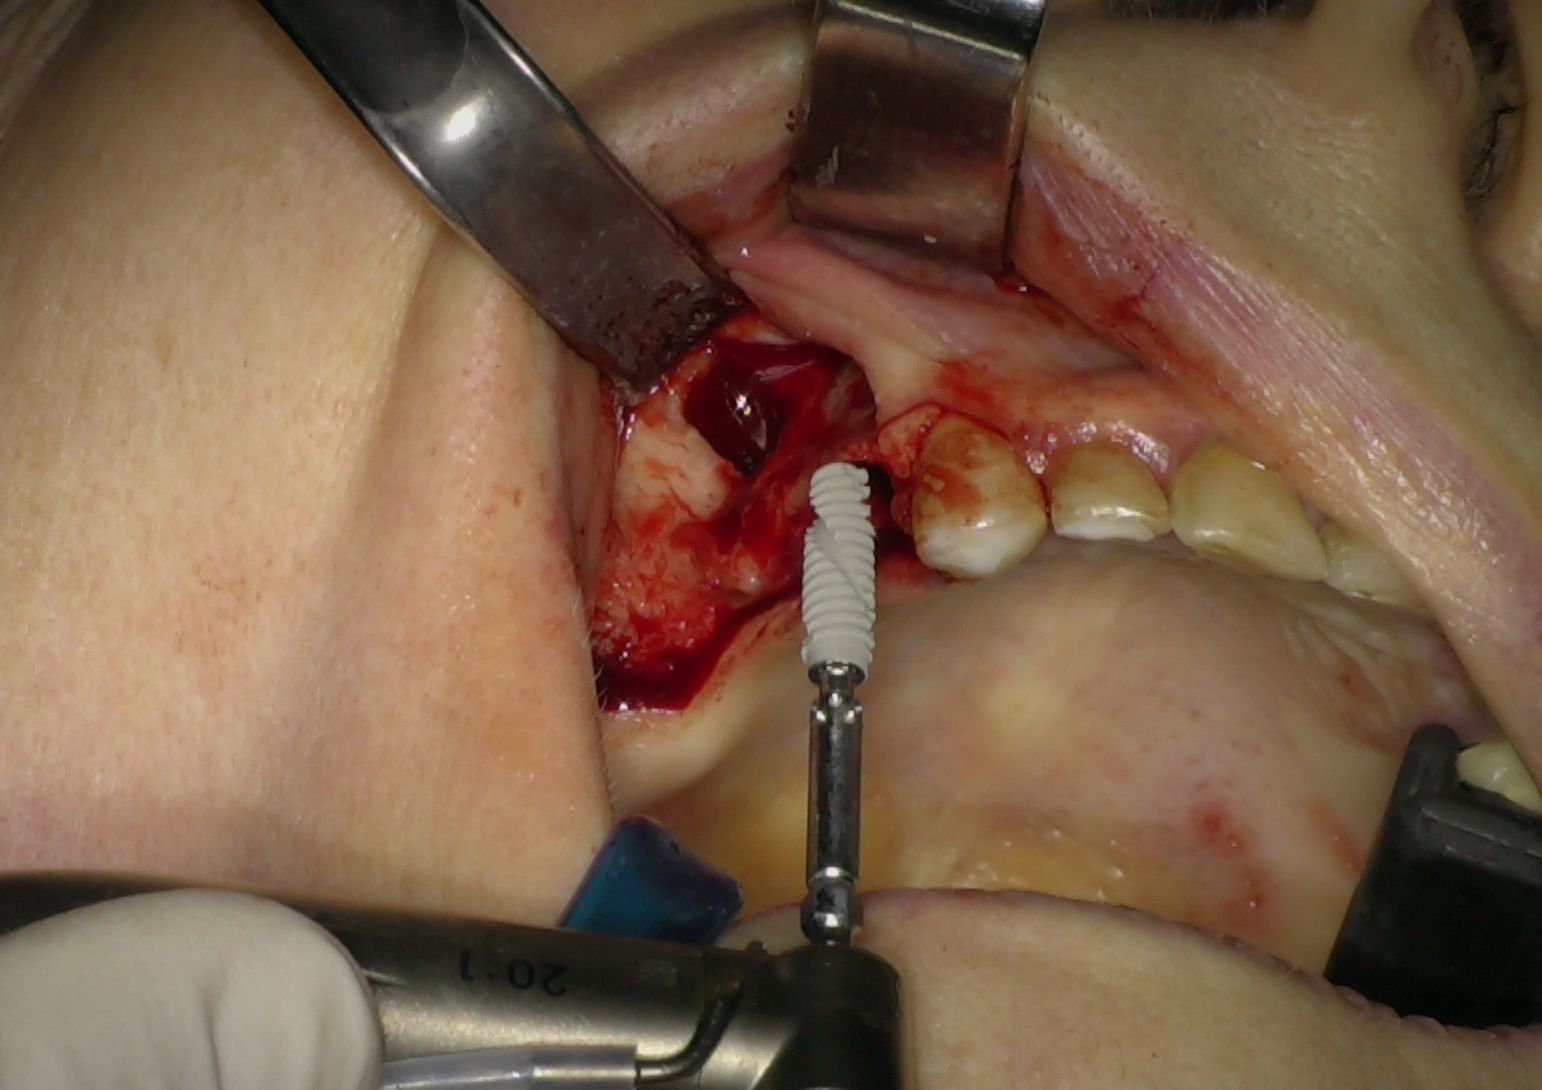

L'intervento chirurgico è stato eseguito in anestesia locali. Dopo il sollevamento di un lembo musopeiosteo a tutto spessore per esporre il mascellare, nei settori anteriori si è proceduto con la preparazione dei siti implantari secondo protocollo convenzionale. Gli impianti IS+ sono stati quindi posizionati (Fig. 2), ottenendo una buona stabilità primaria grazie alla presenza di un adeguato volume di osso residuo.

Fig. 2 - Impianti IS+